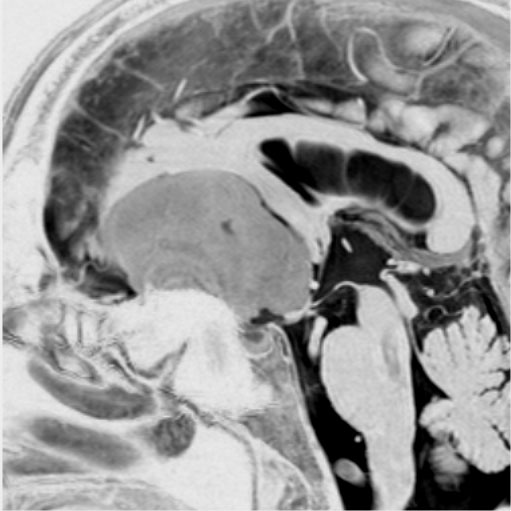

若い女性に偶然発見されたものです。直静脈洞と静脈洞交会の接合部あたりに発生したもので,静脈洞はほぼ閉塞に近い所見でした。しかし,この部分の静脈洞は,テント硬静脈側副路が発達することがあるので,硬膜を含めた積極的な摘出をすることは絶対にできません。もしほんの少しでも流れがある直静脈洞を閉塞させると短時間に脳死になるような脳静脈圧亢進が生じる可能性があるからです。静脈洞内に少し取り残して(右下の矢印)手術を終了しました。手術後には定位放射線治療を行って再増大を防ぎます,